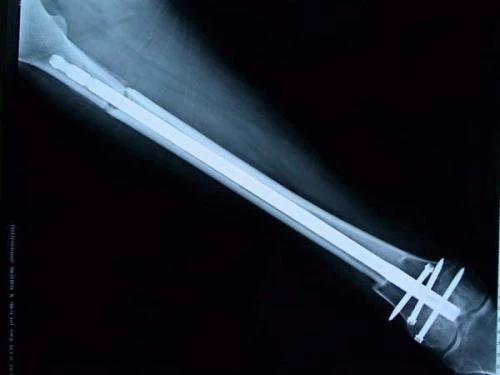

保肢治療指經典型骨肉瘤在多學科團隊醫生共同努力下完成的新輔助化療、保肢手術和輔助化療等一系列治療總稱,其目的是在提高患者生存率的前提下,減少局部復發、盡量保留良好的肢體功能。肢體經典型骨肉瘤保肢治療方法如下圖所示: